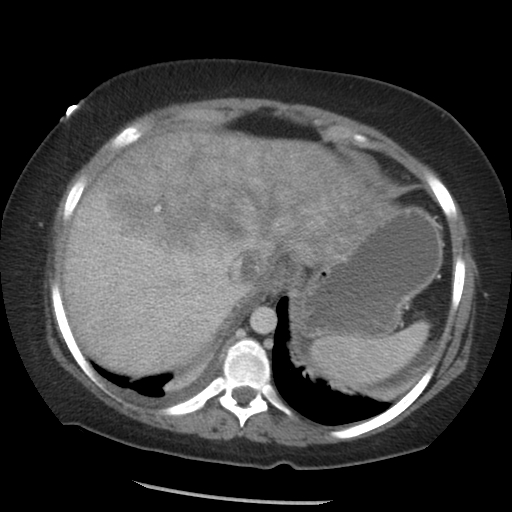

From www.clinicaladvisor.com

Elevated liver enzymes The Clinical Advisor Liver Enzymes Elevated Pancreas Liver function tests in addition to ultrasonography, increased liver enzymes levels provide supportive evidence for gallstones as the cause of. elevated liver enzymes in the setting of acute pancreatitis point toward choledocholithiasis as the cause, with an. chronic pancreatitis is an irreversible and progressive disorder of the pancreas characterized by inflammation, fibrosis,. many diseases, medications and conditions. Liver Enzymes Elevated Pancreas.